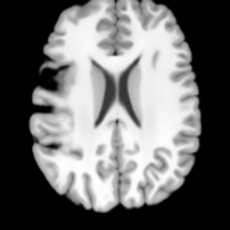

Healthy w/Lesion MaskPathologicalDifferencew/o LCGw/ LCG(a)Refer to captionRefer to captionRefer to captionRefer to captionRefer to captionRefer to captionHealthy w/Lesion MaskPathologicalDifferencew/o LCGw/ LCG(b)Refer to captionRefer to captionRefer to captionRefer to captionRefer to captionRefer to caption

Figure 7: Ablation study of Lesion Consistency Guidance (LCG). Without LCG, the generated pathological regions are indistinct and show weak pathological expression in both examples.

Lesion Consistency Guidance. Fig. 7 illustrates the impact of Lesion Consistency Guidance (LCG) for healthy-to-pathology editing. Without LCG, the generated lesion regions appear blurry around lesion boundaries, and the pathological patterns are less distinct, resulting in ambiguous lesion localization and weak pathological expression. Incorporating LCG produces lesions with more precise localization and well-defined shapes that better align with the given lesion masks, as well as textures and contrasts that exhibit stronger pathological characteristics. These results demonstrate that LCG effectively enforces lesion-aware conditioning, enhancing both spatial and semantic consistency of the generated pathological regions.